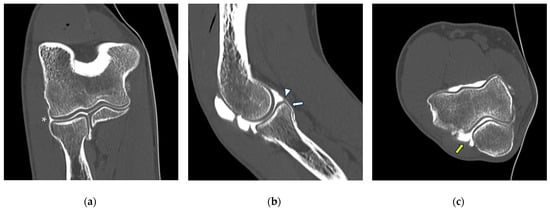

Figure 8.

CT arthrography of a patient with lateral epicondylitis subjected to multiple corticosteroid injections. (a,b) Coronal and axial images show extravasation of intra-articular contrast into lateral periarticular soft tissues through a large full-thickness tear of both the radial collateral ligament and the proximal common extensor tendon (white arrowheads). Diffuse thinning of radial head dish cartilage is also displayed (white arrows); (c) sagittal image also shows distal displacement of the annular ligament (yellow arrowhead) and cartilage fraying of the radial head side (yellow arrow).